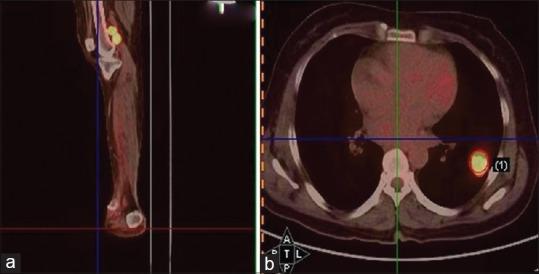

Case report: Non-small-cell lung carcinoma presenting as a foot swelling.

https://cdn.ncbi.nlm.nih.gov/pmc/blobs/516a/4429399/f367fb80a674/LI-32-292-g001.jpg